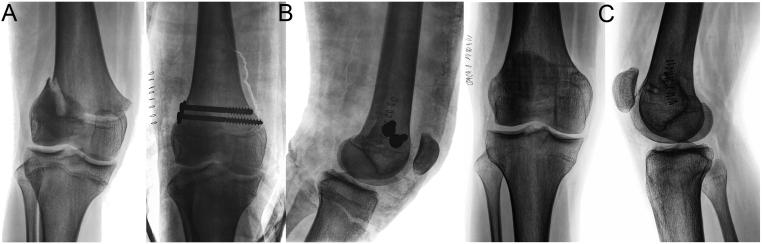

The physis of the distal femur contributes to 70% of femoral growth and 37% of the total limb growth; therefore, physeal injury can lead to important alterations of axes and length. Distal metaphyseal corner-type fracture prior to walking is classically associated with child abuse. In children aged >10 years, sports-related fractures and car accidents are significant contributors. Imaging includes a two-plane radiographic study of the knee. It is recommended to obtain radiographs that include the entire femur to rule out concomitant injuries. In cases of high suspicion of distal metaphyseal fractures and no radiographic evidence, CT or MRI can show the existence of hidden fractures. Fractures with physeal involvement are conventionally classified according to the Salter-Harris classification, but the Peterson classification is also recommended as it includes special subgroups. Conservative and surgical management are valid alternatives for the treatment of these fractures. Choosing between both alternatives depends on factors related to the fracture type. As there is a high risk of permanent physeal damage, long-term follow-up is essential until skeletal maturity is complete.

股骨远端的生长板对股骨生长的贡献率为70%,对整个肢体生长的贡献率为37%;因此,生长板损伤可导致轴线和长度的重要改变。行走前的远端干骺端角型骨折通常与虐待儿童有关。在10岁以上的儿童中,与运动相关的骨折和车祸是重要原因。影像学检查包括膝关节的双平面X线检查。建议获取包括整个股骨的X线片以排除合并损伤。在高度怀疑远端干骺端骨折但无X线证据的情况下,CT或MRI可显示隐匿性骨折的存在。涉及生长板的骨折传统上根据Salter-Harris分类法进行分类,但也推荐使用Peterson分类法,因为它包括特殊的亚组。保守治疗和手术治疗都是治疗这些骨折的有效选择。在这两种选择之间做出决定取决于与骨折类型相关的因素。由于存在永久性生长板损伤的高风险,因此在骨骼成熟完全之前进行长期随访至关重要。